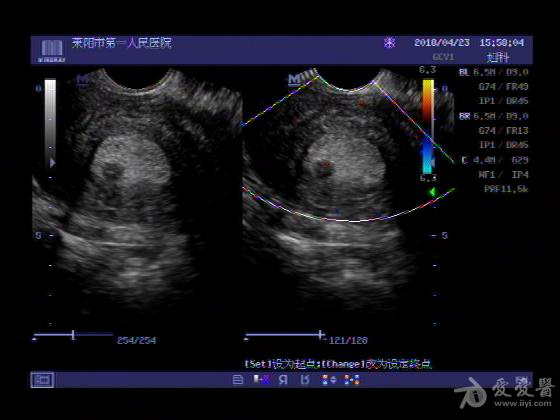

女,48岁,月经量多,两个月,一年前出现过类似现象,刮宫吃药后缓解。

超声可见:子宫内膜显著增厚,后肌壁内膜可见范围约3.27X0.90CM低回声区,CDFI显示较丰富线样血流,宫底宫腔内见类**状低回声结节。前肌壁见多发类圆形低回声结节。

超声提示:子宫内膜增厚(建议刮宫病理),子宫多发肌瘤

病理结果:内膜增生